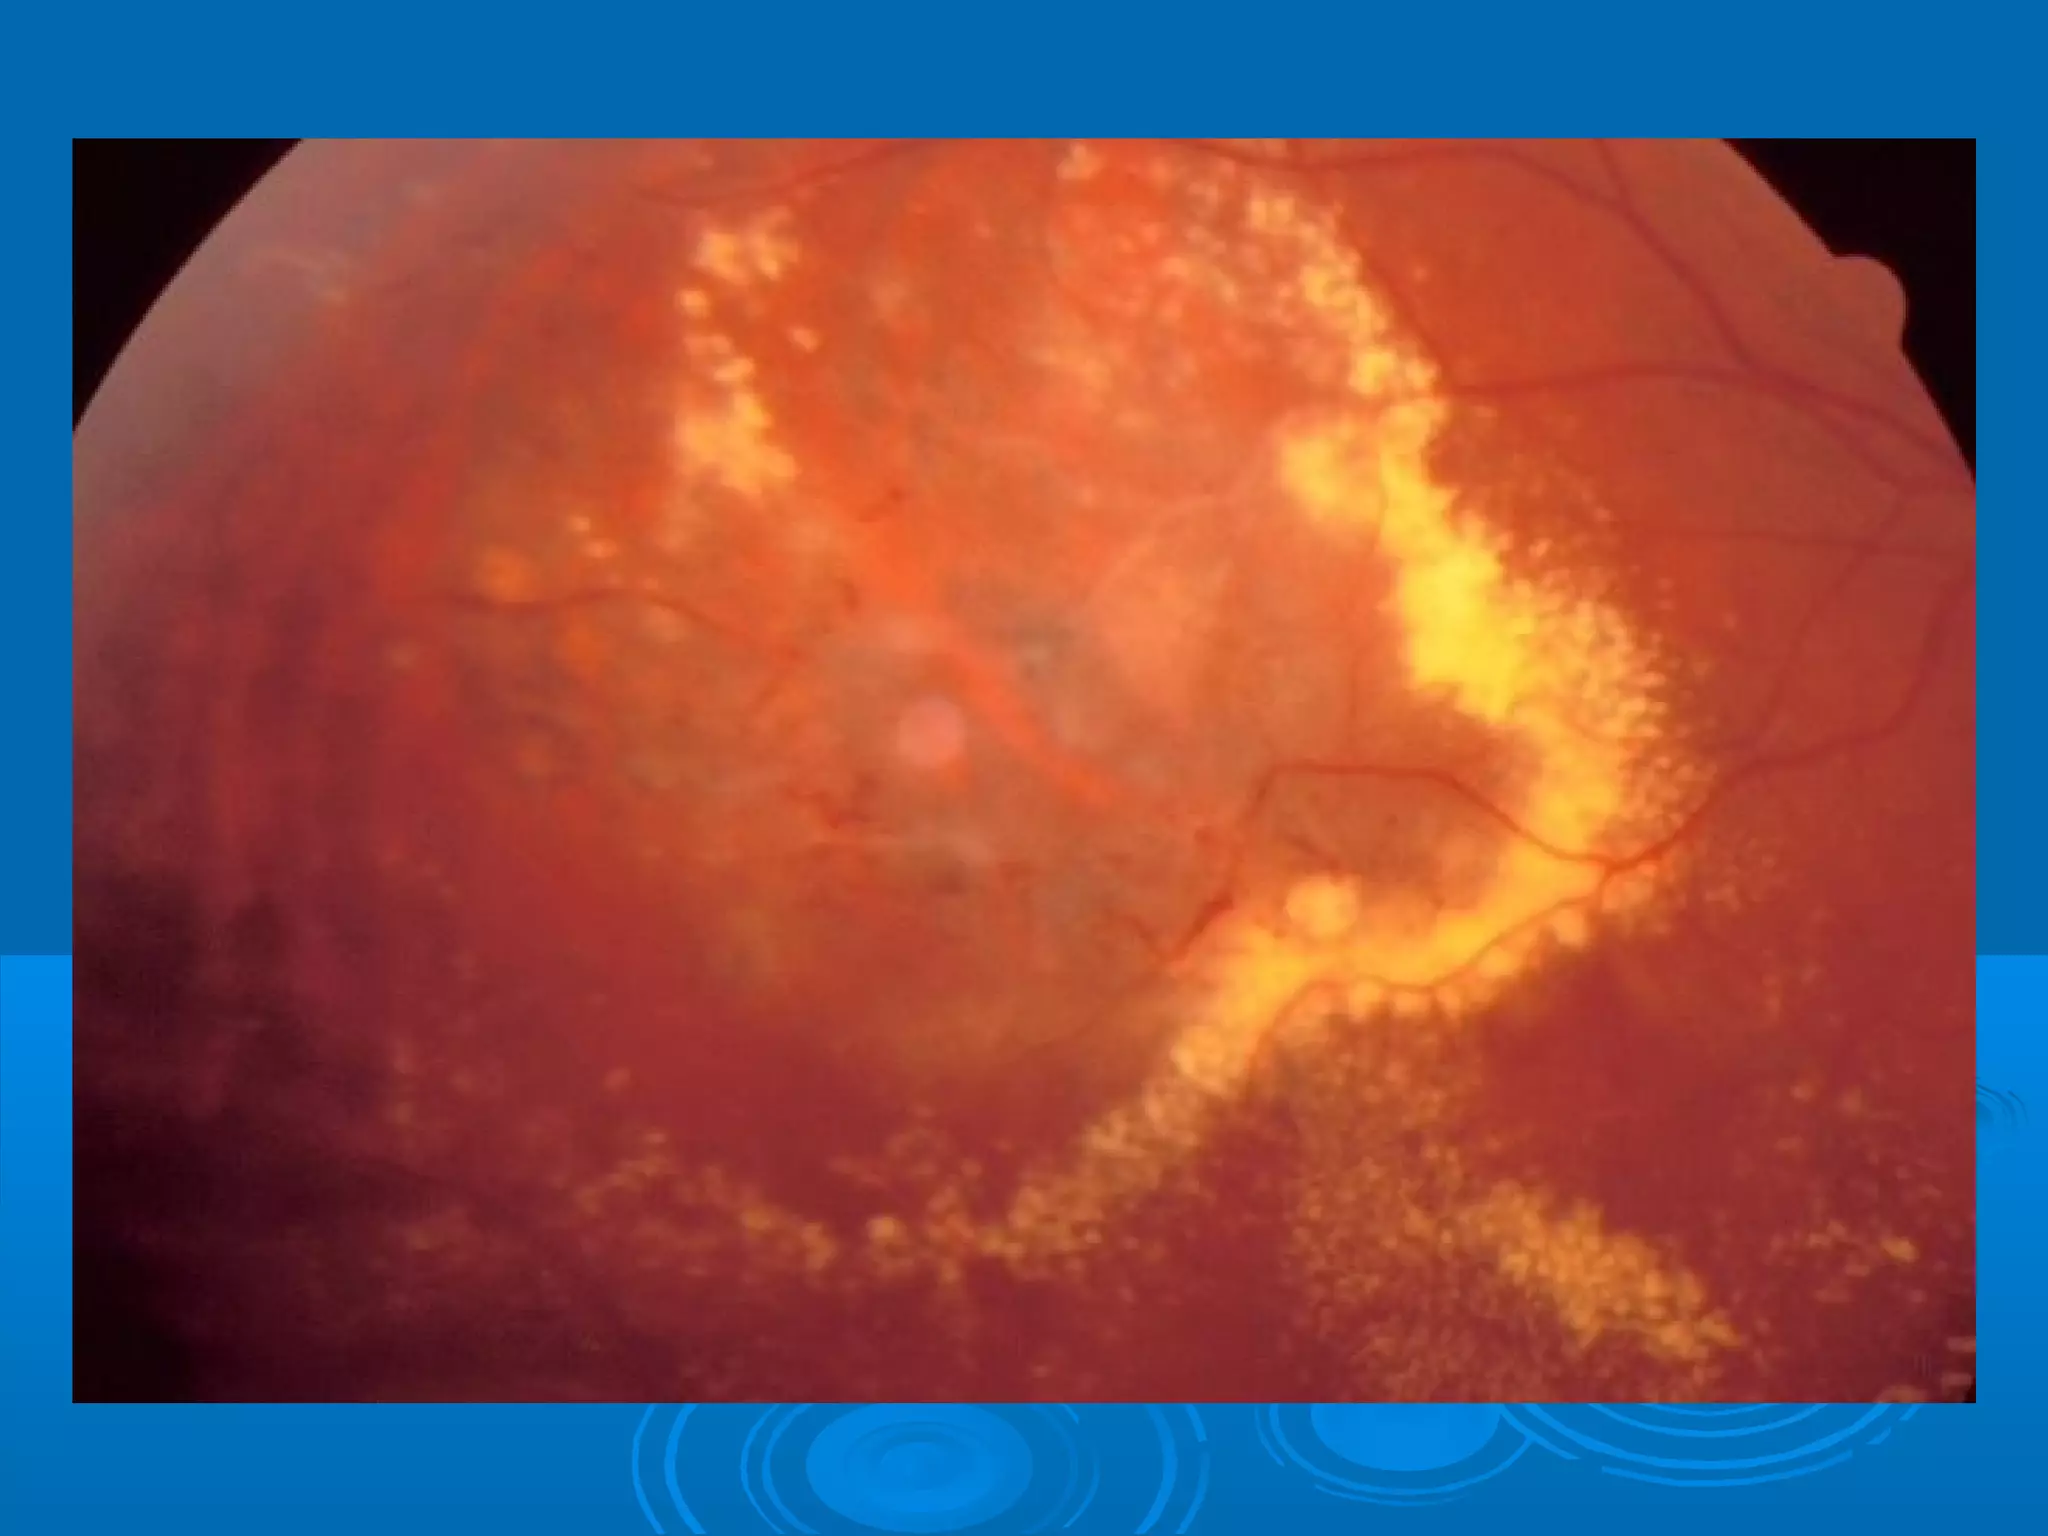

Болезнь Коатса - это идеопатическое заболевание, характеризующееся полиморфными изменениями сосудов сетчатки с массивной экссудацией, чаще всего у детей и подростков, с преобладанием среди мальчиков. Эпидемиология показывает, что заболевание проявляется, как правило, в возрасте 8-16 лет, но возможно его обнаружение и у взрослых. Основные проявления включают ретинальные аномалии, субретинальную экссудацию и постепенно прогрессирующую потерю зрения.